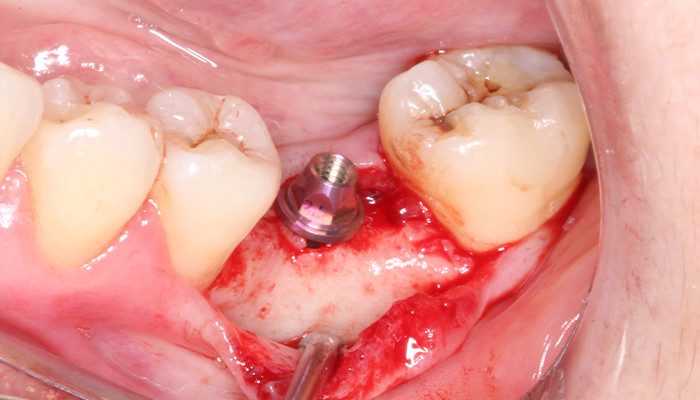

8 | Implantes instalados 2 mm infraósseo.

9 | Verificação do torque de instalação do implante 36.